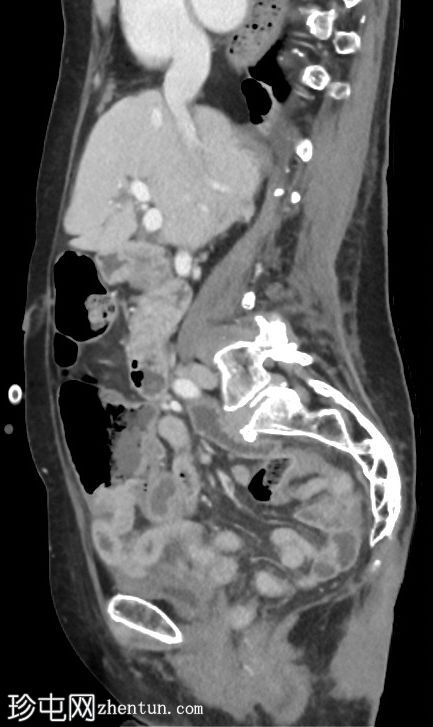

矢状C+门静脉期

阑尾盲肠极-基底部明显增厚,强化明显。阑尾中段1/3直径扩张至12毫米,远端1/3增厚。阑尾尖端周围有微小组织性液体积聚。阑尾周围无明显脂肪条带。

轻度门静脉周围血流痕迹。大量胆结石。L2-L3-L4节段后路椎板切除术后,因L2-L3节段大量钙化性椎间盘突出释放压力。子宫脱垂术后。腰椎侧凸,向左凸。